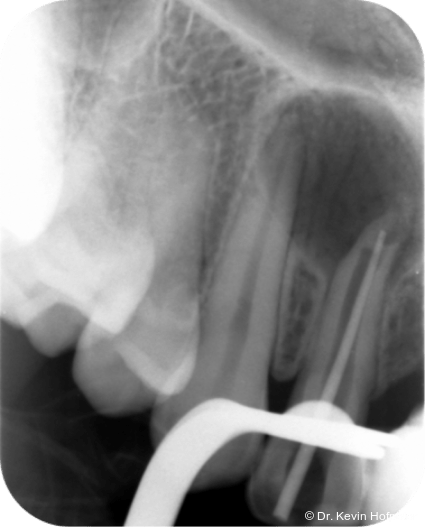

Klinisch zeigten sich die Zähne 12 und 13 karies- und füllungsfrei. Zahn 12 reagierte nicht auf Sensibilitätstests und war leicht perkussionsempfindlich. Zahn 13 reagierte unauffällig. Radiologisch zeigte sich eine ausgedehnte apikale Aufhellung am Zahn 12 sowie eine Hartgewebsformation im apikalen Kanallumen (Abb. 1–2d).

Geplant wurde eine Wurzelkanalbehandlung an Zahn 12. Die zunächst vorgesehene Zystektomie mit Wurzelspitzenresektion wurde zurückgestellt, um die Heilungstendenz nach orthograder Therapie zu beurteilen und einen chirurgischen Eingriff möglichst zu vermeiden.